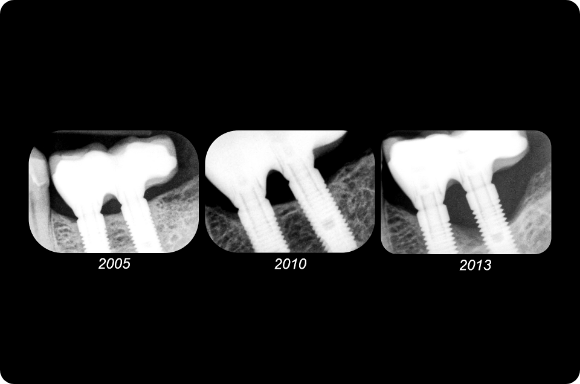

Ce cours de niveau maîtrise aborde à la fois la prévention et la gestion des complications chirurgicales et restauratrices. Dans le domaine chirurgical, la présentation se concentre sur l’échec précoce de l’implant et la maladie péri-implantaire ultérieure. Les concepts prothétiques comprendront la conception de prothèses préventives, le retrait des vis/piliers et un séquençage qui reconnaît l’importance de l’expérience du patient.